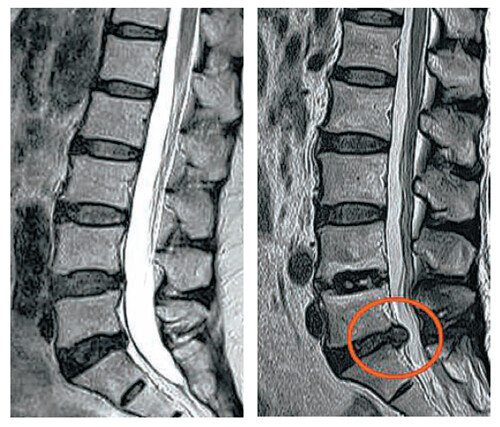

허리디스크는 척추의 구조를 이해하는 것이 중요합니다. 척추는 여러 개의 척추뼈로 이루어져 있으며, 이 사이에 디스크가 위치하고 있습니다. 디스크는 젤리같이 부풀어 있는 내부와 외부 섬유링으로 이루어져 있어 충격을 흡수하는 역할을 합니다. 그러나 여러 요인, 예를 들어 무리한 운동, 잘못된 자세, 노화 등으로 인해 디스크가 손상되거나 탈출하게 되면 심각한 통증을 유발할 수 있습니다.

허리디스크 증상은 다양한 형태로 나타날 수 있으며, 이를 통해 문제가 발생하고 있음을 인식할 수 있습니다. 일반적으로 허리디스크의 증상은 허리 통증, 다리 저림, 근력 약화, 통증의 위치에 따라 다양하게 나타나기 때문에 이러한 사항들을 잘 이해해야 합니다.